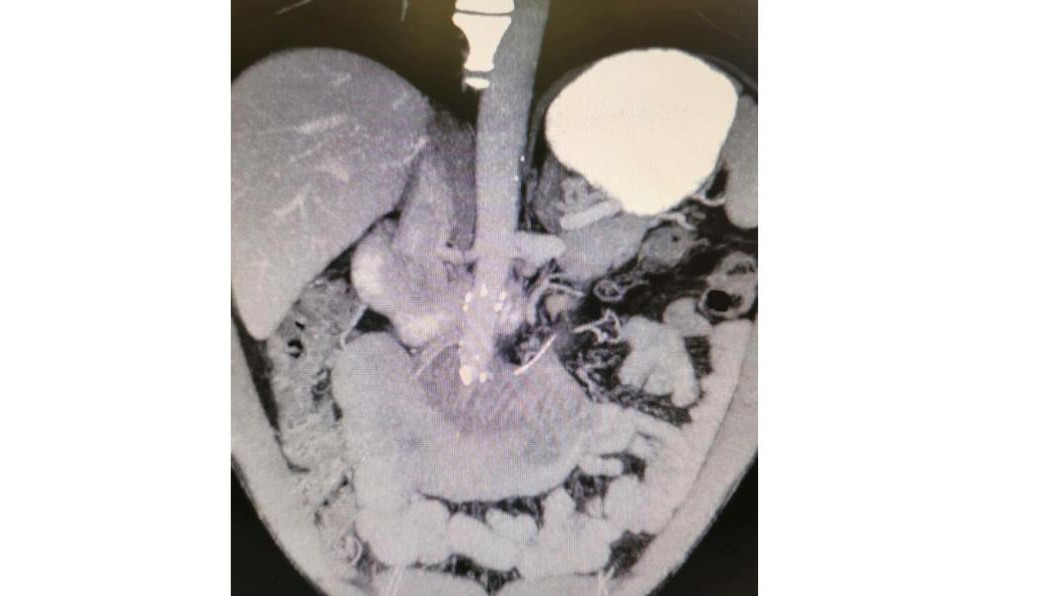

В РКБ ему сделали МРТ и повели на операцию. В итоге выяснили, что кость проткнула кишечник и вышла в брюшную полость.

— Хирурги аккуратно удалили кость, зашили кишечник и перевели пациента в палату. Через несколько дней мужчину в удовлетворительном состоянии выписали домой, – рассказали в пресс-службе РКБ.